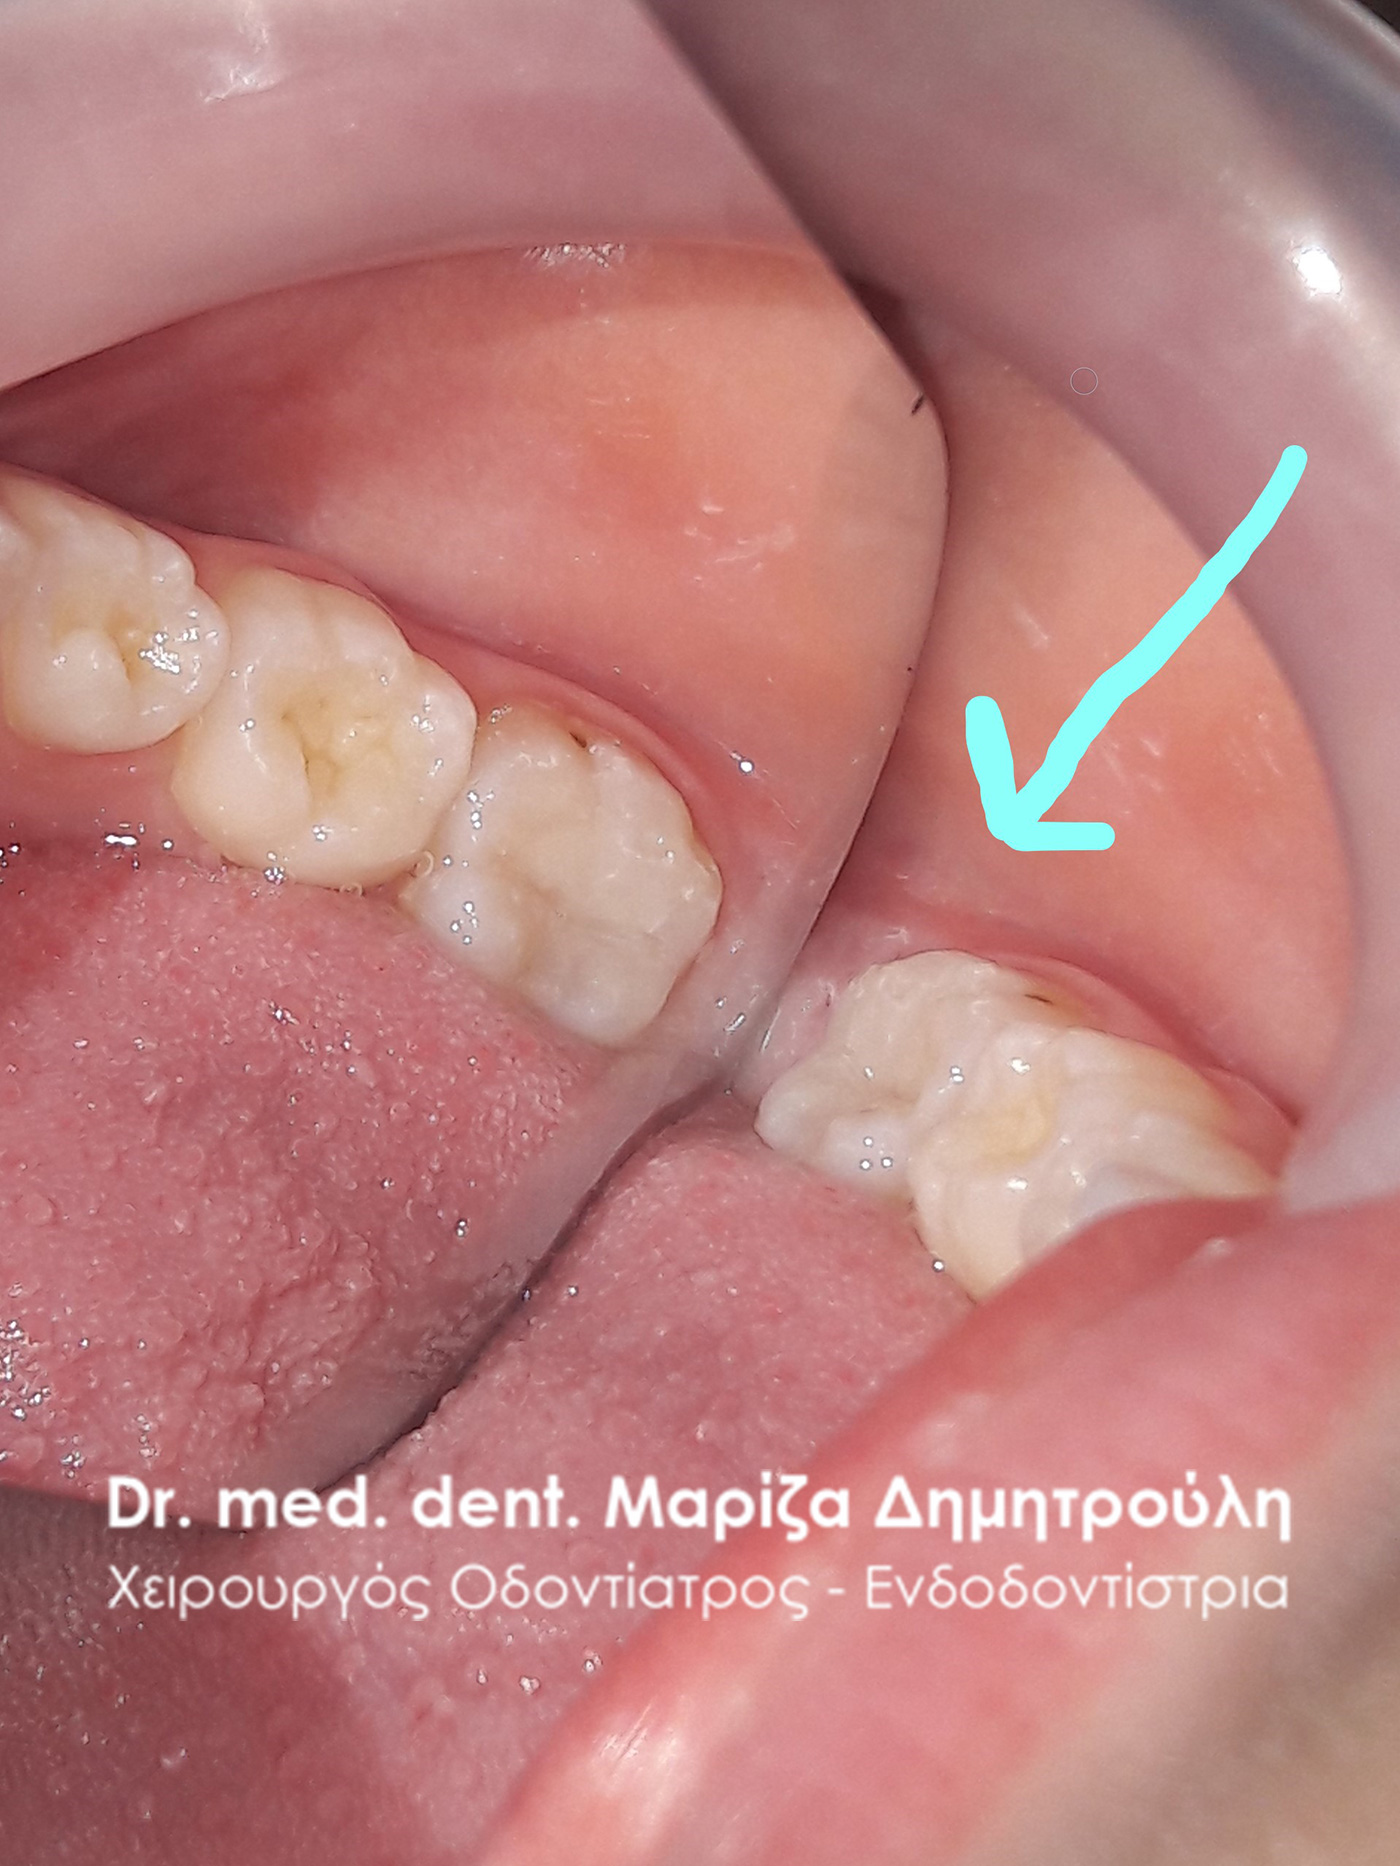

Dental filling of primary tooth

BEFORE

AFTER